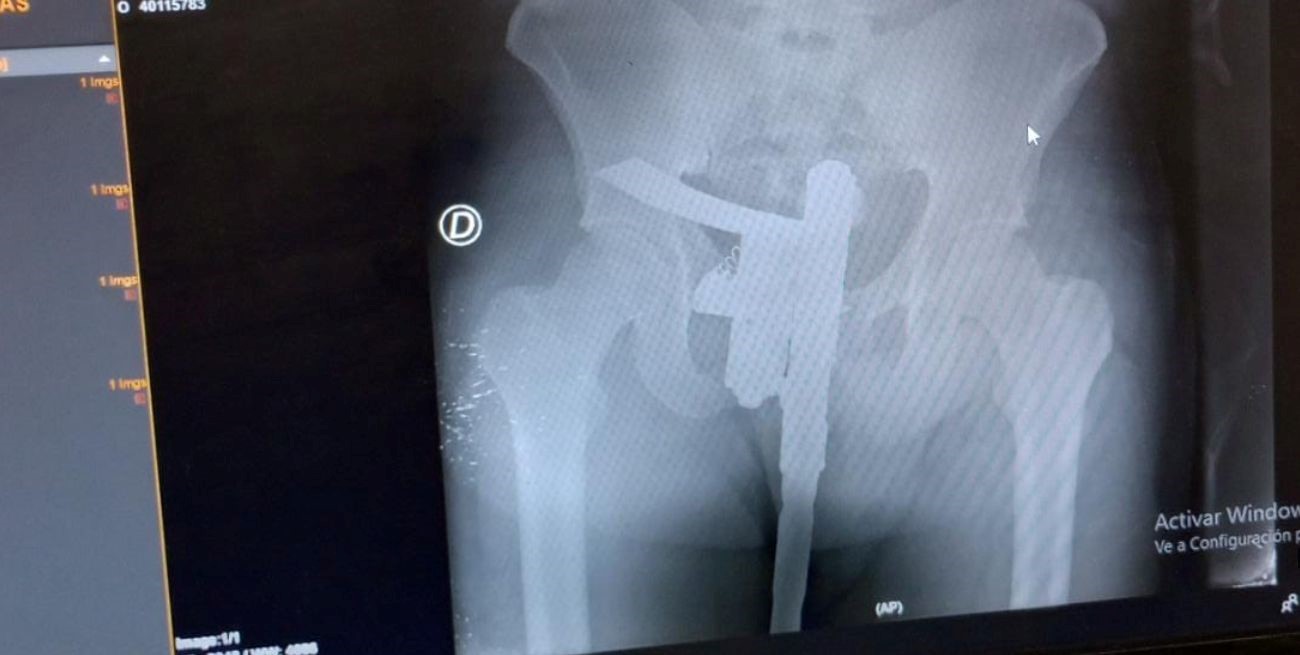

Como es de rutina un médico hizo una primera evaluación y, como el paciente manifestaba dolor en la zona de la cadera, se ordenó realizar una placa radiográfica.

El estudio se concretó de manera normal, aunque minutos después el revelado permitió descubrir una "sorpresa". En la placa se observó que el paciente tenía un arma de fuego oculta entre sus genitales.